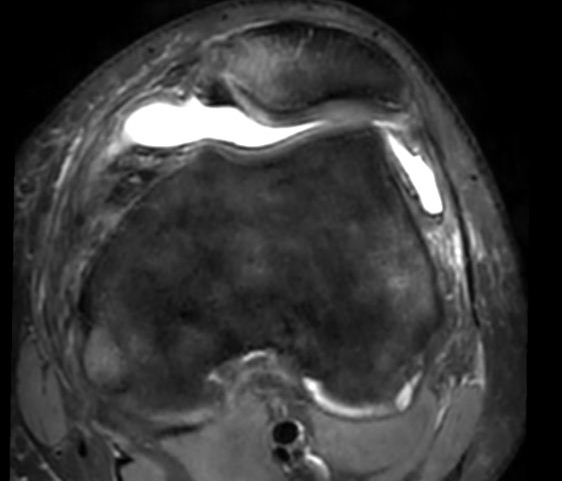

内侧髌骨韧带关节镜下重建后,术中在关节镜下观察,髌骨已经复位良好,术后MRI影像学表现如下:

术前髌骨半脱位状态            术后髌骨复位